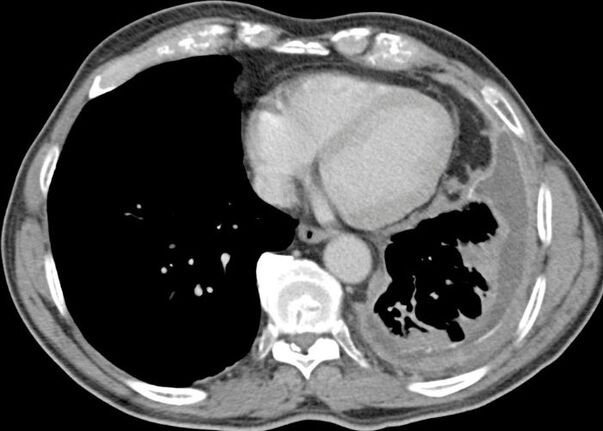

A thoracoscopic biopsy of the pleura using Video-Assisted Thoracoscopy (VATS) is the preferred diagnosis technique. Patients are sometimes diagnosed after a pleurocentesis, or procedure where fluid surrounding the lungs (if present) is drained and then analyzed. CT Scans are also effective and often used for detecting and diagnosing pleural mesothelioma.